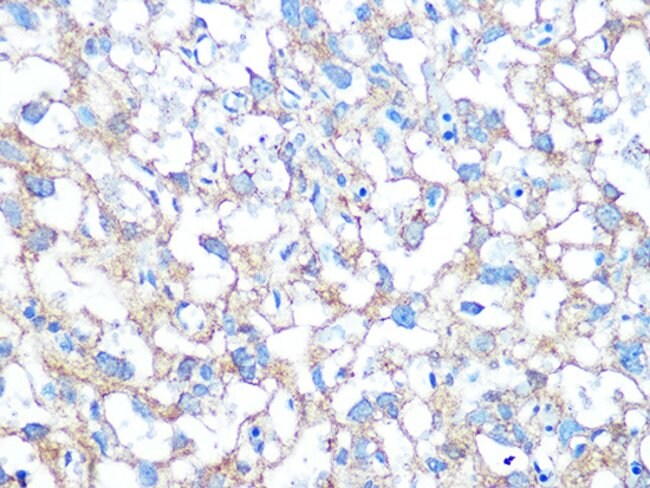

PLAP Antibody (Immunohistochemistry)

The PLAP (Placental Alkaline Phosphatase) Antibody is an important IHC marker.

It helps identify germ cell tumors and related neoplasms with high diagnostic value.

Moreover, PLAP positivity commonly appears in Seminoma,

Embryonal Carcinoma, and Placental Site Trophoblastic Tumors.

As a result, its membrane or cytoplasmic staining pattern becomes a strong indicator of germ cell origin.

- Clear brown membrane or cytoplasmic staining in positive cells